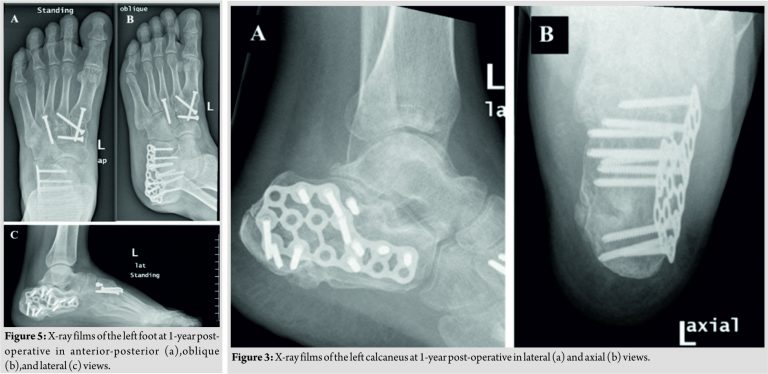

The patient then underwent ORIF utilizing an extended lateral approach. Using a 3.5 mm K-wire inserted posteriorly, the posterior fragment and the articular surface were reduced under fluoroscopy supervision. A medium calcaneal plate was then applied and held in place with screws locking and non-locking. A back slab was applied and the patient was discharged 2days after the operation. Outpatient follow-up 4months postoperatively shows healing skin over the posterior aspect of the calcaneus (Fig. 3b). At 1-year post-operative visit, the patient is back to complete daily activities with mild pain while running. Radiographs of the calcaneus and the Lisfranc fractures showed good fixation and healing (Fig. 5 and 6).